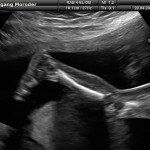

Con l’ecografia transvaginale è possibile vedere dopo circa 3 settimane dal concepimento la camera gestazionale nella cavità uterina. Successivamente è possibile visualizzare l’embrione (3-5 mm.) a circa 6 settimane dall’ultima mestruazione (4 settimane dal concepimento) ed a questo periodo è già visibile l’attività cardiaca fetale Anche i primi dettagli sulla morfologia fetale (polo cefalico, abbozzi degli arti) sono visualizzabili più precocemente con l’ecografia transvaginale, risultando essi visibili intorno a 8-9 settimane.